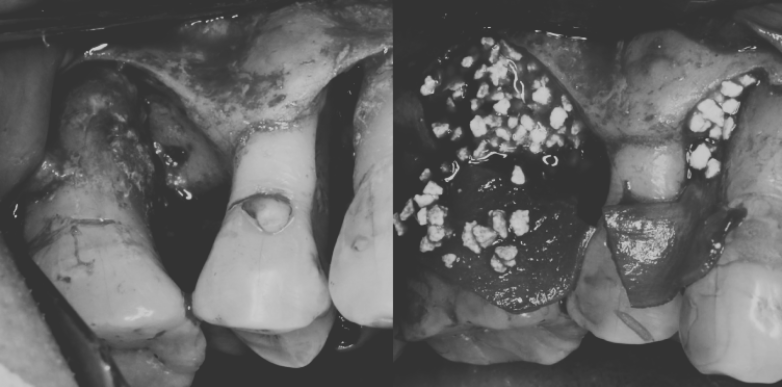

複合的な感染源を断つ|

50代 女性

マイクロスコープ精密根管治療と再生療法の併用症例

治療名 【歯周・歯内複合病変】組織再生療法+精密根管治療 治療期間 約1年 執刀医 Dr. 大杉 治療費 420,000円(税込)

■内訳:

再生療法 250,000円

根管治療 130,000円

支台築造 40,000円治療解説 歯の内部と歯周組織の両方に感染が及んでおり、抜歯判断になりやすいケースに対して保存を前提に治療を行いました。

まず精密根管治療で感染源を除去・封鎖し、その後に歯周組織再生療法を実施。

内外の感染を段階的にコントロールすることで、抜歯回避と安定化を目指しました。リスク・副作用 神経(歯髄)を除去するため、歯への栄養供給が断たれ、健全歯に比べて強度が低下します。

硬いものを噛んだ際などに歯根破折のリスクが伴う。 -